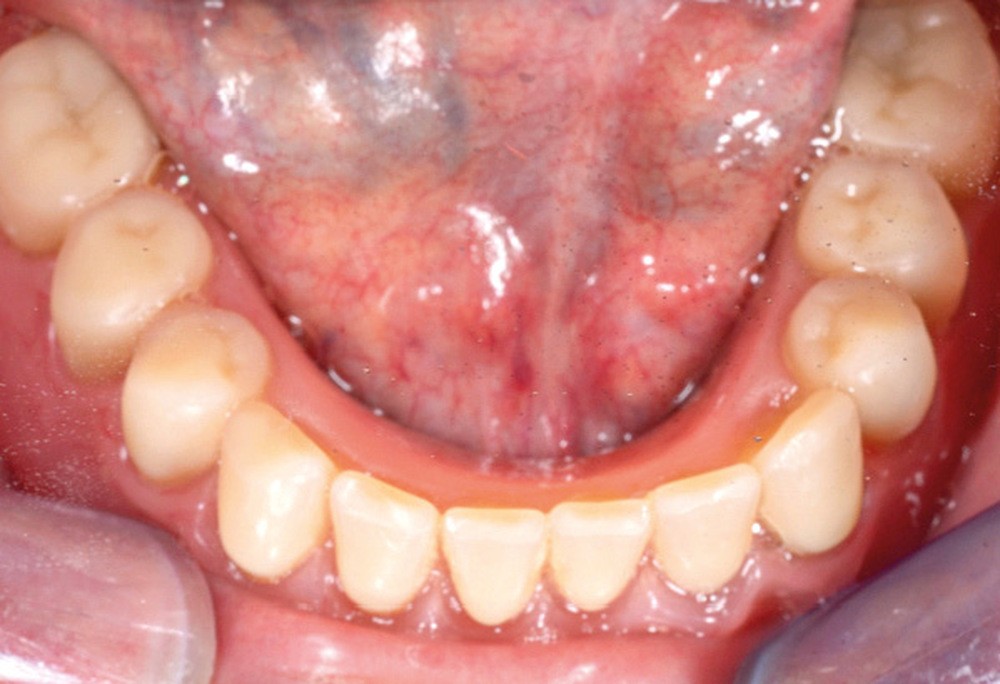

Dans le cas clinique présenté dans cet article, le patient édenté total bimaxillaire se plaint d’une gêne importante et d’une insatisfaction de son sourire en lien avec un plan d’occlusion prothétique inadapté (fig. 1 et 2).

En prothèse amovible complète, le plan d’occlusion correspond au plan selon lequel seront montées les dents prothétiques. En règle générale, il passe par le bord libre des deux incisives centrales et le bord distal des deuxièmes molaires inférieures [2]. Outre des répercussions d’ordre esthétique, un plan d’occlusion erroné peut perturber la cinématique mandibulaire, générer un inconfort, une impotence, voire un handicap fonctionnel. Des conséquences pathologiques à long terme telles que des myoarthropathies de l’appareil manducateur peuvent aussi se manifester [2].